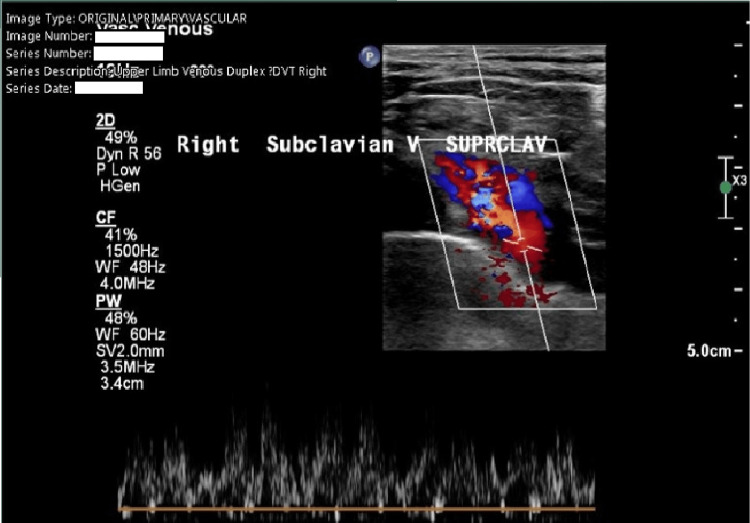

We discuss the case of a 36-year-old woman who presented with persistent right upper limb swelling and pain. A previous negative D-dimer (434 µg/L (normal range <500 µg/L)) resulted in an inappropriate discharge, despite a significant past medical history. The patient was sent for a right upper limb ultrasound Doppler scan due to persistent pain, and a clot in the right supraclavicular subclavian vein was observed, confirming the diagnosis of Paget-Schroetter syndrome (PSS). The clot was successfully removed under the vascular team in Cardiff without any post-op complications. The literature review demonstrates that PSS should be suspected mostly on a clinical basis; the literature does not support the use of a D-dimer to support a suspected upper limb deep vein thrombosis (DVT), as this could delay vital treatment for the patient, as demonstrated in this case.